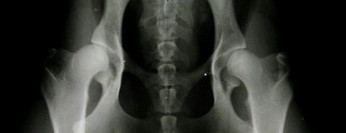

D - dysplazja częściowa tzw. ograniczona gdzie wyraźnie rozpoznaje się nadwichniecie będące wynikiem dysplazji

D - dysplazja częściowa tzw. ograniczona gdzie wyraźnie rozpoznaje się nadwichniecie będące wynikiem dysplazji.